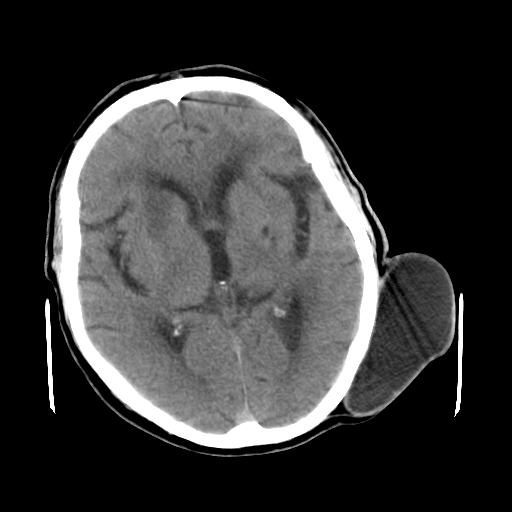

男,62岁,右侧肢体活动障碍不灵活三天,左侧头皮肿物十余年(ct值8hu)。

多发腔梗!皮下脂肪瘤!

1)多发性腔隙性脑梗塞。2)脑白质病。3)脑萎缩。4)左侧枕顶部头皮下皮样囊肿,不排除脂肪瘤。

1)多发性腔隙性脑梗塞。2)脑白质病。3)脑萎缩。4)左侧枕顶部头皮下皮样囊肿或表皮样囊肿。